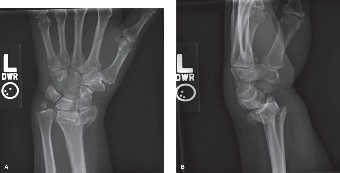

A 67-year-old, left-hand-dominant, retired female sustained a left distal radius fracture when she tripped in…